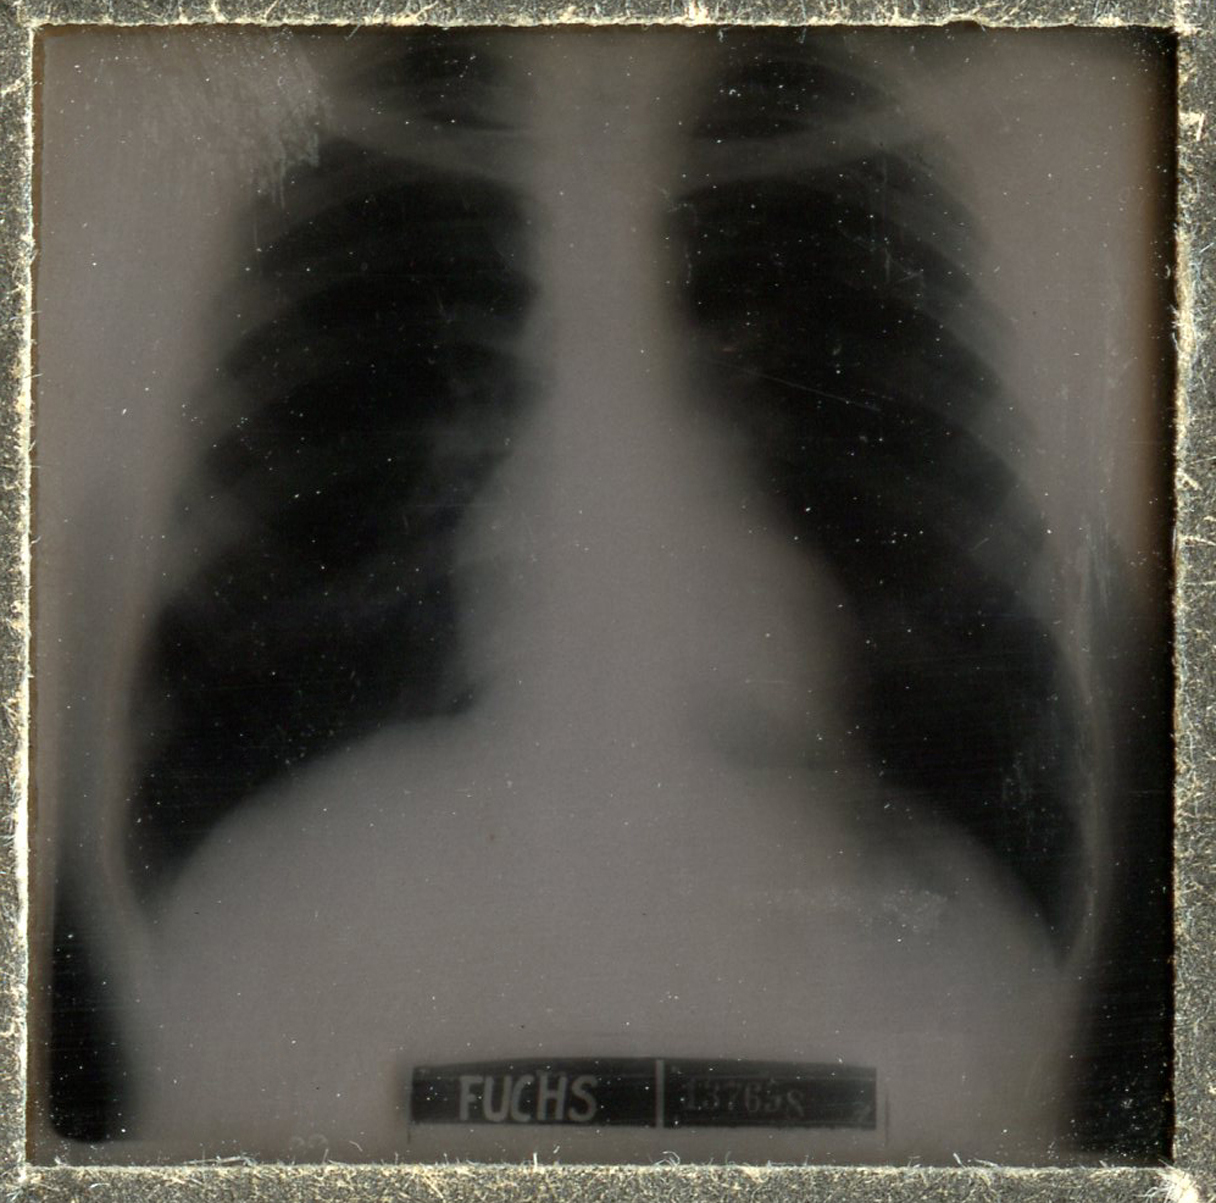

[Below: X-ray in pocket of booklet - side A. X-rays were discovered in 1895 by the German scientist Wilhelm Röntgen.]

[Below: X-ray in pocket of booklet - side B.]

[Below: X-ray close-up.]

[Below: Diagram of injuries - side A. This diagram lists extensive lung problems/injuries. For example, our soldier, Michael Fuchs, didn't have full lung capacity and had a rattle, among other problems. But it must have went away and was fixed because he is still a soldier in 1943.]